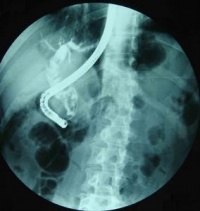

4.静脉胆道造影、PTC(经皮肝穿刺胆道造影术)、ERCP、CT等检查,显示胆管扩张,有结石影。可有胆总管下段部分梗阻、排空迟缓征象。

1.X线平片胆总管的原发结石和继发结石,分别是以胆色素和胆固醇为主的混合结石。X线平片不能显示。

2.口服或静脉胆道造影胆管的影像浅淡,难以作出准确诊断。

5.ERCP和PTC检查均可清晰显示胆管系统的全貌,能比较准确提供肝内外胆管和胆囊结石的大小、数量、位置以及肝内外胆管扩张、狭窄等病理改变状况,是获得术前准确诊断最重要的检查方法。ERCP基本无创、并发症较少,PTC为有创、并发症稍多,可根据病人和病变的具体情况选择。一般情况下多选择ERCP检查。